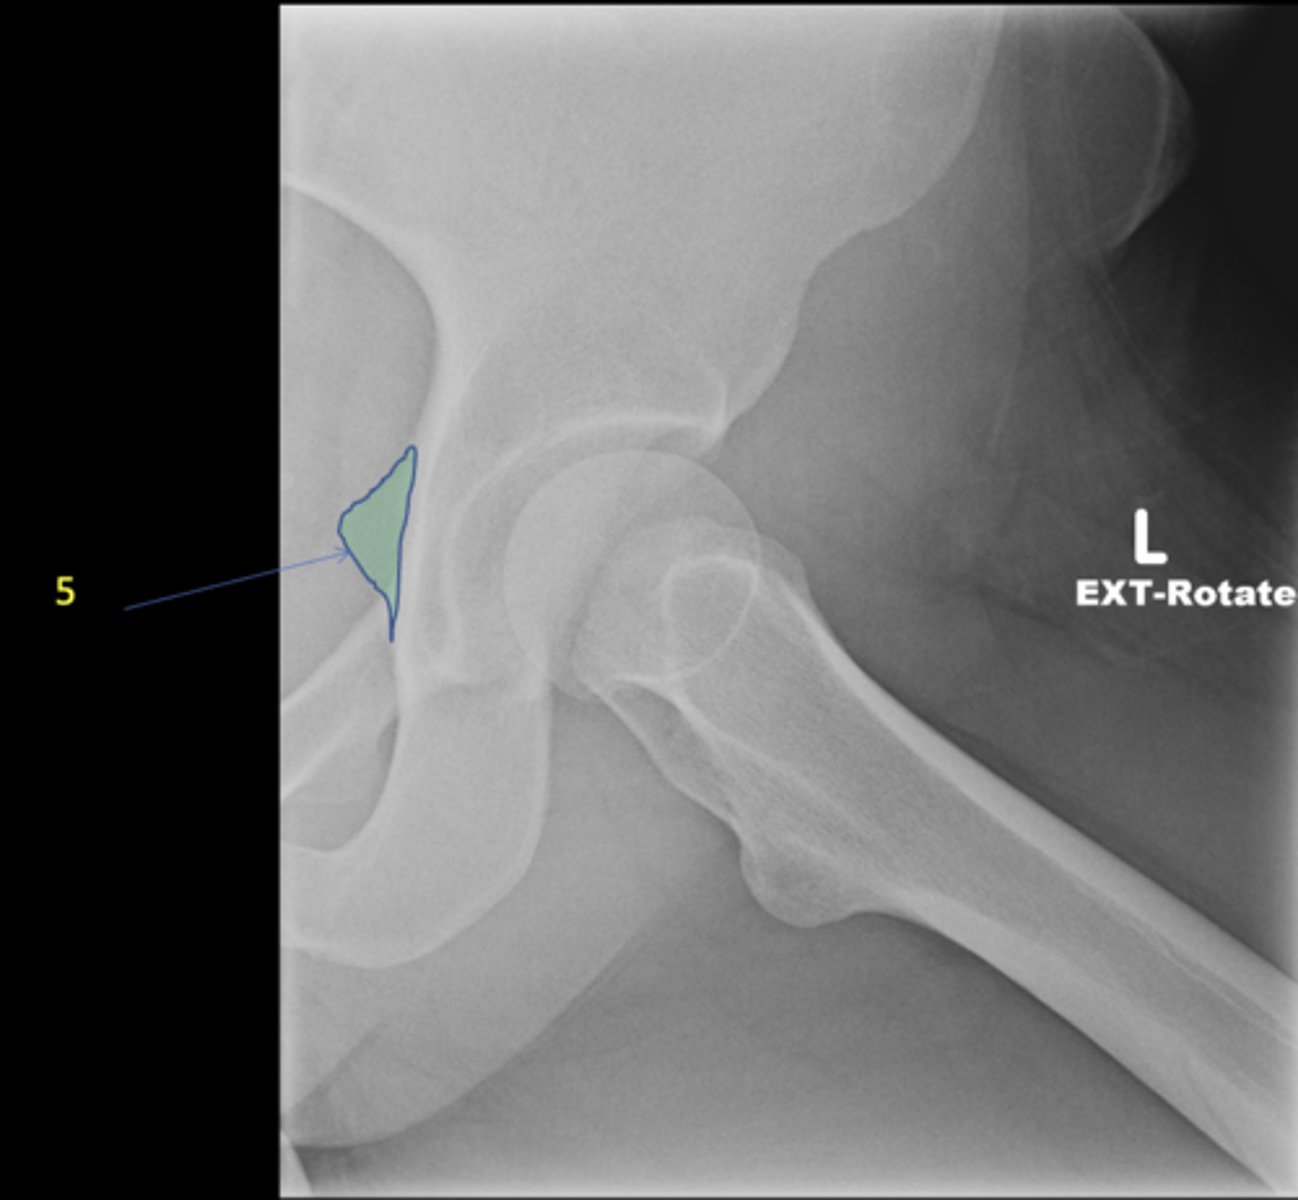

Left AP hip

View?

<p>View?</p>

33

New cards

Ischial tuberosity

ID 5

<p>ID 5</p>